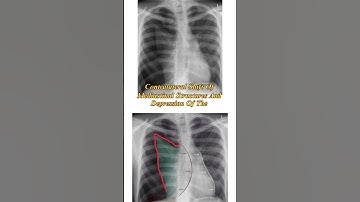

Signature Assignment - Pneumothorax